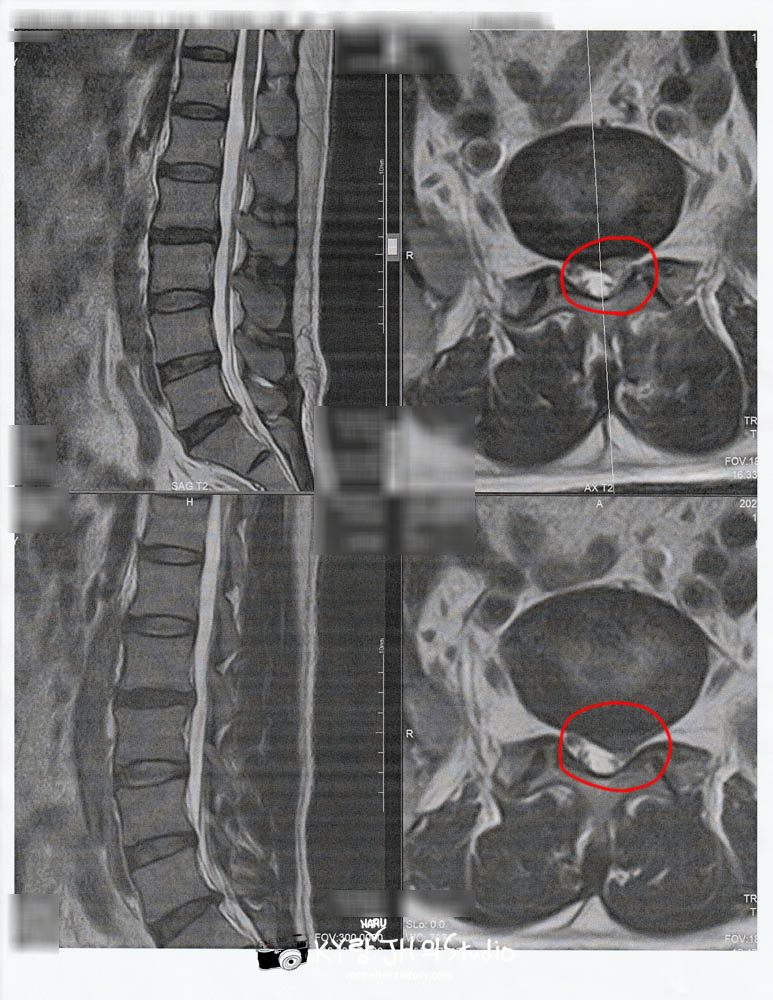

금요일은 다시 휴가를 내고 수술 후 경과 관찰을 위해 다시 병원에 들려서 MRI도 찍고 수술 부위를 확인했는데 수술 부위도 문제없으니 오늘부터 진통제 안 먹어도 되고 목욕도 해도 되지만 한 달 정도는 재발 가능성이 있으니 운동이나 과격하게 움직이지 말고 조심하고 한달 뒤에 다시 경과 확인을 위한 X레이 검사 예약을 하고 집으로 왔습니다.

아래 사진진은 수술 후(위)와 수술 전(아래)의 비교 사진으로 신경을 누르고 있던 추간판이 제거된 걸 확인할 수 있습니다